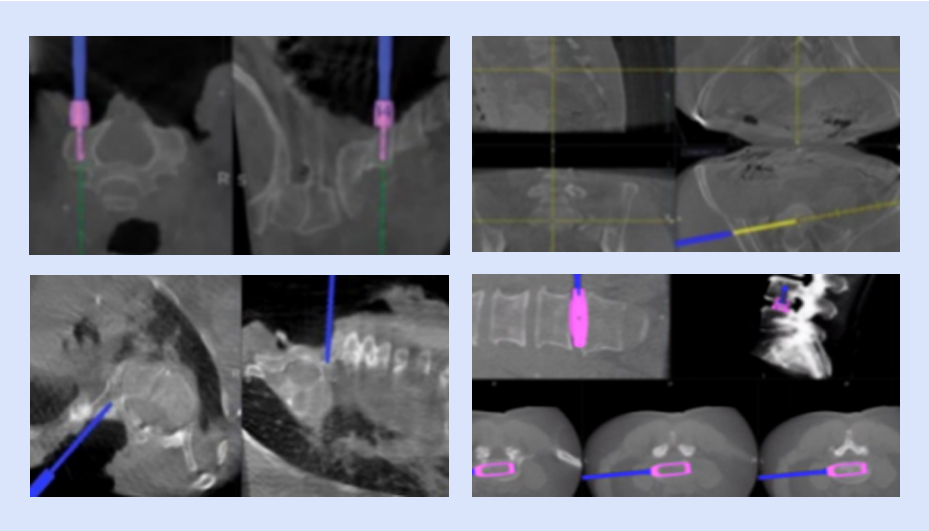

可視化置釘

確保導(dǎo)航設(shè)備正常運(yùn)行,檢查定位系統(tǒng)、手術(shù)器械、置釘系統(tǒng)等是否完好,以及設(shè)備是否處于最佳工作狀態(tài)

可視化椎間融合

具備全套導(dǎo)航專用椎間融合工具,實(shí)現(xiàn)從椎間隙定位、放置通道、椎間處理、試模、放置融合器的全程可視化,提高手術(shù)效率,做到精準(zhǔn)融合。